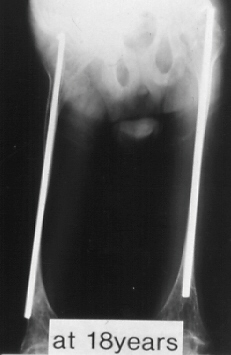

This 9 year old boy presented with the diagnosis of osteogenesis imperfecta. By age nine he sustained 16 fractures in his lower extremities and 30 fractures in his upper extremities. He started walking at 18 months of age. He now complains of pain in the ankle. At this time he is a household and minimal community ambulator. Following this fracture he did not walk and presented at age 18 with these x-rays. The diameter of the right and left femur at the age of 18 years were 7 and 8 mm's respectively.